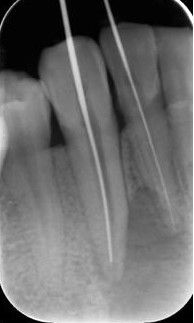

三、确定根管工作长度

应用平行投照X线方法、根管长度测量仪确定根管度,最好插针拍X片

确定根管工作长度